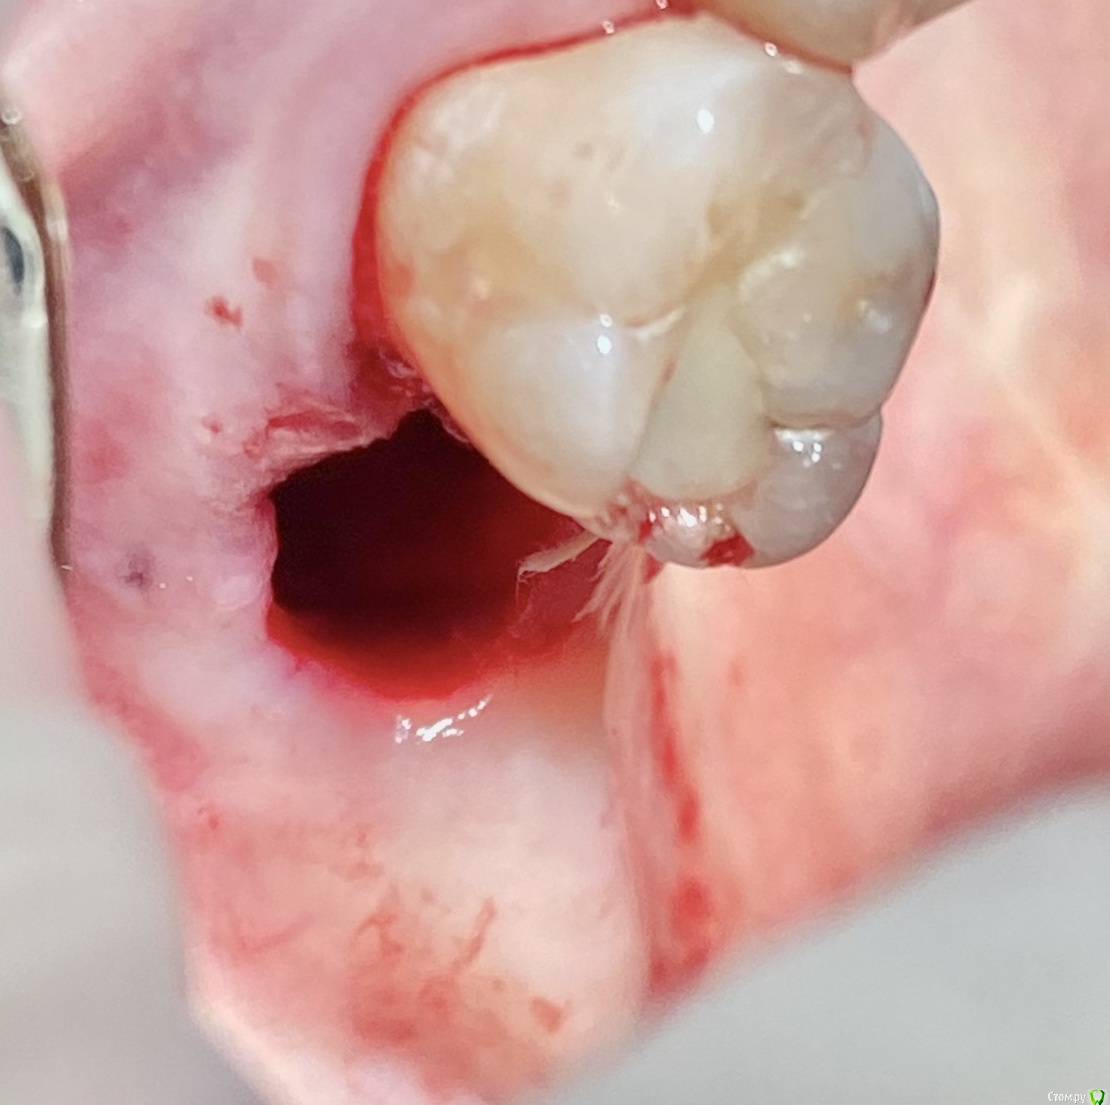

колесников Опубликовано 11 сентября, 2020 Поделиться Опубликовано 11 сентября, 2020 Перемещение бугра для закрытия лунки. Вестибулярно прикрепленную не смещаем. Вестибулярно компактной пластинки нет 9 Ссылка на комментарий

колесников Опубликовано 27 сентября, 2020 Поделиться Опубликовано 27 сентября, 2020 Вид через 2 недели Ссылка на комментарий